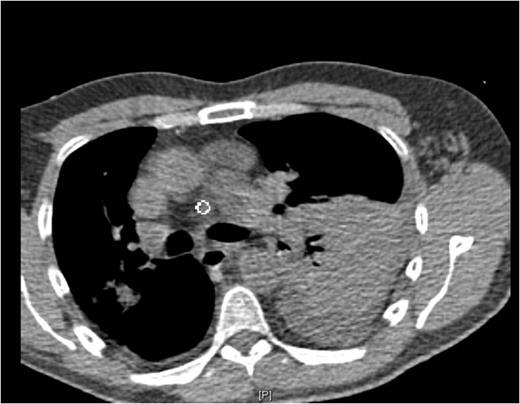

Chest pain persisted and the patient required higher pressure CPAP to maintain adequate oxygenation. Auscultation consistently showed decreased air-entry in the lung bases. On day 3, a repeat chest x-ray showed a left lower lobe collapse above the gastric bubble in the mid zone of the chest (Fig. 4 & 5). CTPA done on the same day to exclude pulmonary embolism confirmed a para-oesophageal hernia that was pushing against the left lung base. Ultrasound scan of the left chest also showed movement of the diaphragm below the gastric bubble.

Chest x-ray on 3rd post-op day showing prominent left sided collapse/ consolidation

Post-op CT-scan demonstrating the left sided pleural effusion with collapse /consolidation & patchy opacification on the right side.